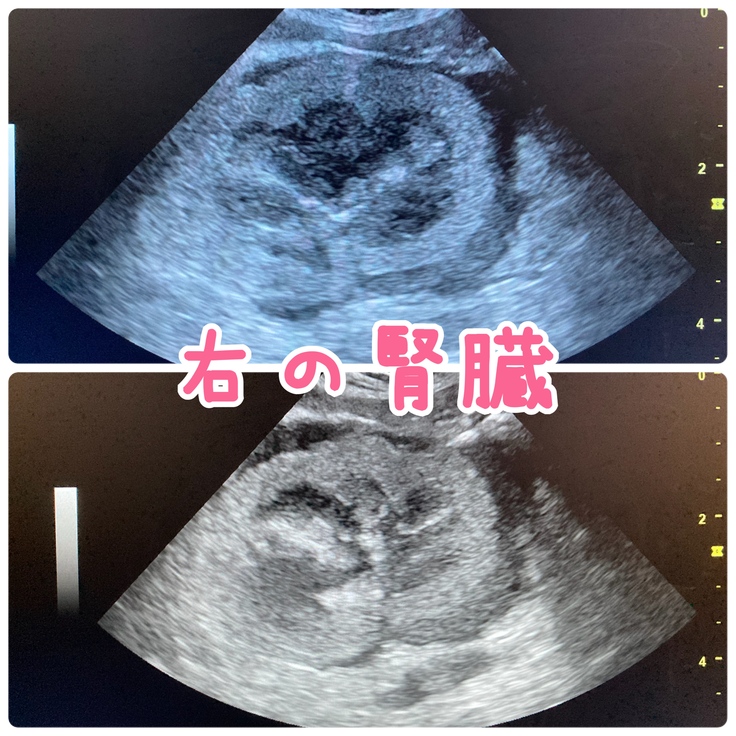

1/6に経過観察で受診をし、血液検査とエコー検査したところ

リンパ腫が転移した腎臓の状態は1週間前よりも悪くなっていました。

もしかしたら、腎臓以外の臓器にも転移している可能性が考えられると担当獣医に言われました。